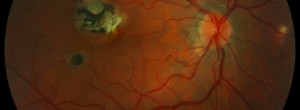

A Swine Model of Selective Geographic Atrophy of Outer Retinal Layers Mimicking Atrophic AMD: A Phase I Escalating Dose of Subretinal Sodium Iodate